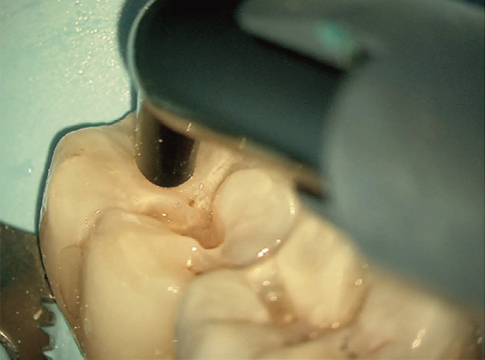

See in True Light

NoGlare mode(オプション)

EXTARO 300は偏光照明を用いて拡大視野下での観察を初めて実現した手術顕微鏡です。この照明により歯の色調を正確に確認することができ、また歯表面からの反射を低減します。

拡大視野